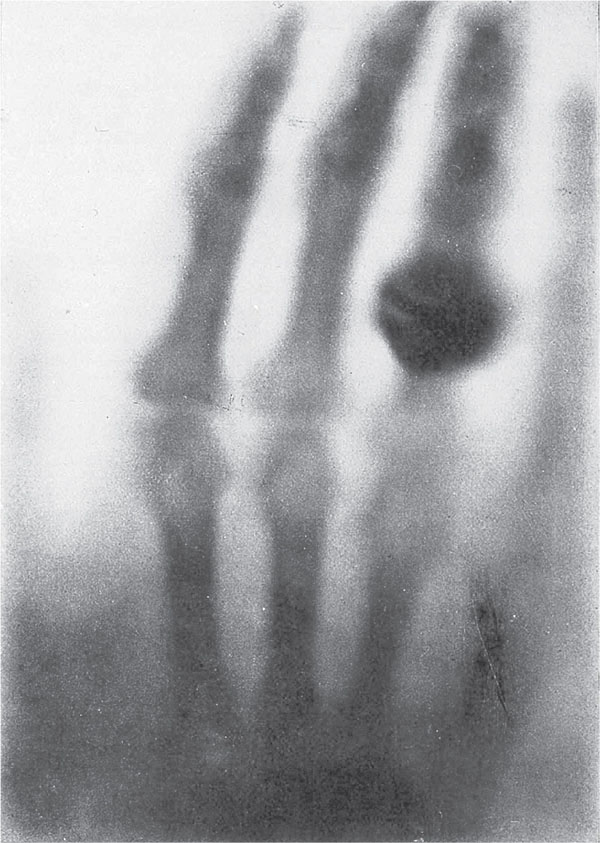

А трубка Крукса продолжала подсвечивать бариевые пластинки, несмотря на то что Рентген отказывался в это поверить. И вот ученый принялся документировать этот феномен. Опять же, в отличие от трех описанных выше эпизодов патологической науки, Рентген игнорировал любые мимолетные или несистематические эффекты – все, что могло оказаться субъективным. Он добивался лишь объективных результатов, например, экспериментировал с проявленными фотопластинками. Наконец, уже обретя некоторую уверенность, однажды вечером он пригласил в лабораторию Берту и подставил под таинственные лучи ее руку. Женщина, увидев свои кости, просто ужаснулась, решив, что это предзнаменование смерти. После этого она отказывалась входить в эту жуткую лабораторию, но ее реакция оказала на Рентгена неизгладимое впечатление. Возможно, это был самый значительный поступок, который Берта совершила для мужа, – а Рентген убедился, что не выдумал всего этого.

На одном из первых рентгеновских снимков мы видим кости и замечательное кольцо Берты Рентген, жены Вильгельма Рентгена. Вильгельм, опасавшийся, что сошел с ума, успокоился, когда супруга тоже увидела свои кости на покрытой барием пластинке. Она, будучи не такой отважной, приняла этот снимок за предзнаменование смерти